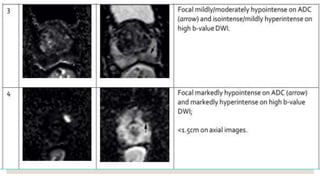

◦ 3: focal mildly/moderately hypointense on ADC and isointense/mildly hyperintense on high b-value DWI

◦ 4: focal markedly hypointense on ADC hyperintense on high b-value DWI; <1.5 cm in greatest

dimension

◦ 5: same as 4 but ≥1.5 cm in greatest dimension or definite extraprostatic extension/invasive behavior